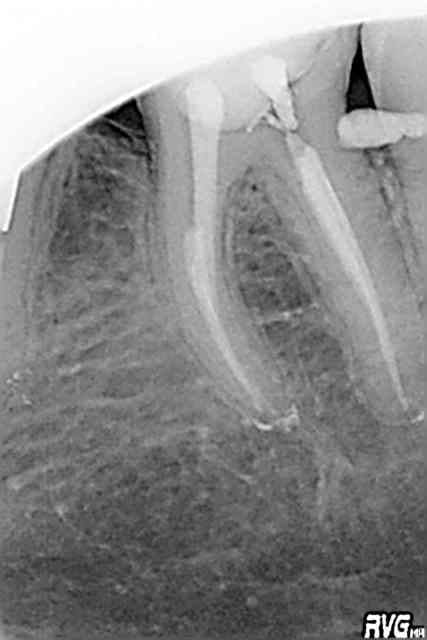

c'est vrai je n'ai pas mis toutes les chances du coté du patient : mais bon allez regardons un peu plus la radio

cette dent est versée et pour pouvori faire u ne reconstitution "étanche" il faudra dans un premier temps la distaler ou bien faire une élongation coronaire mattes bien "guttaman" le niveau infraosseux en mésial et tu verras que j'ai raison.

Tres jolies les endos !

C'était pas gagné sur la 46 ! Joli !

PS: le résultat sur 46 est en grande partie du à l'extraction de 47, pas à mon endo ;-(

> c'est vrai je n'ai pas mis toutes les chances du coté du patient : mais bon

> allez regardons un peu plus la radio cette dent est versée et pour pouvori faire u ne reconstitution "étanche" il

> faudra dans un premier temps la distaler ou bien faire une élongation coronaire

> mattes bien "guttaman" le niveau infraosseux en mésial et tu verras que j'ai

> raison.

Tu as raison. Tu savais ce qu'il fallait faire et tu as fais différemment. C'est ton choix. Désolé si tu le prends mal et que certains y voit un ton hautain dans ce que je dis. Moi je vois que tu n'as pas fais ton maximum par rapport à ce que tu sais faire et c'est dommage pour ce patient là.

Si ta carie est juxta crestale, tu aurais du extraire. Maintenant, tu vas faire quoi ? Mettre un amalgame magnifiquement sculpté ou une couronne ? Les deux provoqueront des saignements ou une "gêne" à la mastication parce que ton espace biologique n'est pas respecté.

L'élongation coronaire me semble compliquée vue la proximité de la racine de 46.